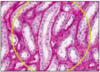

LOOP OF HENLE (PAS)

- mostly @ medulla

- thick/straight descending, thin loop, thick ascending

- thick descend = similar to proximal tubule

- thick ascend = similar to distal tubule

- longest thin loop penetrate deepest to medulla when glomerulus = cortico-medulla junction

- thin descending portion = low permeability to ions and urea, high permeability to water

- thin ascending portion retains water, reabsorption Na+ and Cl-

- this produces dilute/hypotonic filtrate but a hypertonic interstitium

- vasa recta (straight capillaries) run alongside tubules

this slide - thick and thin limbs and vasa recta